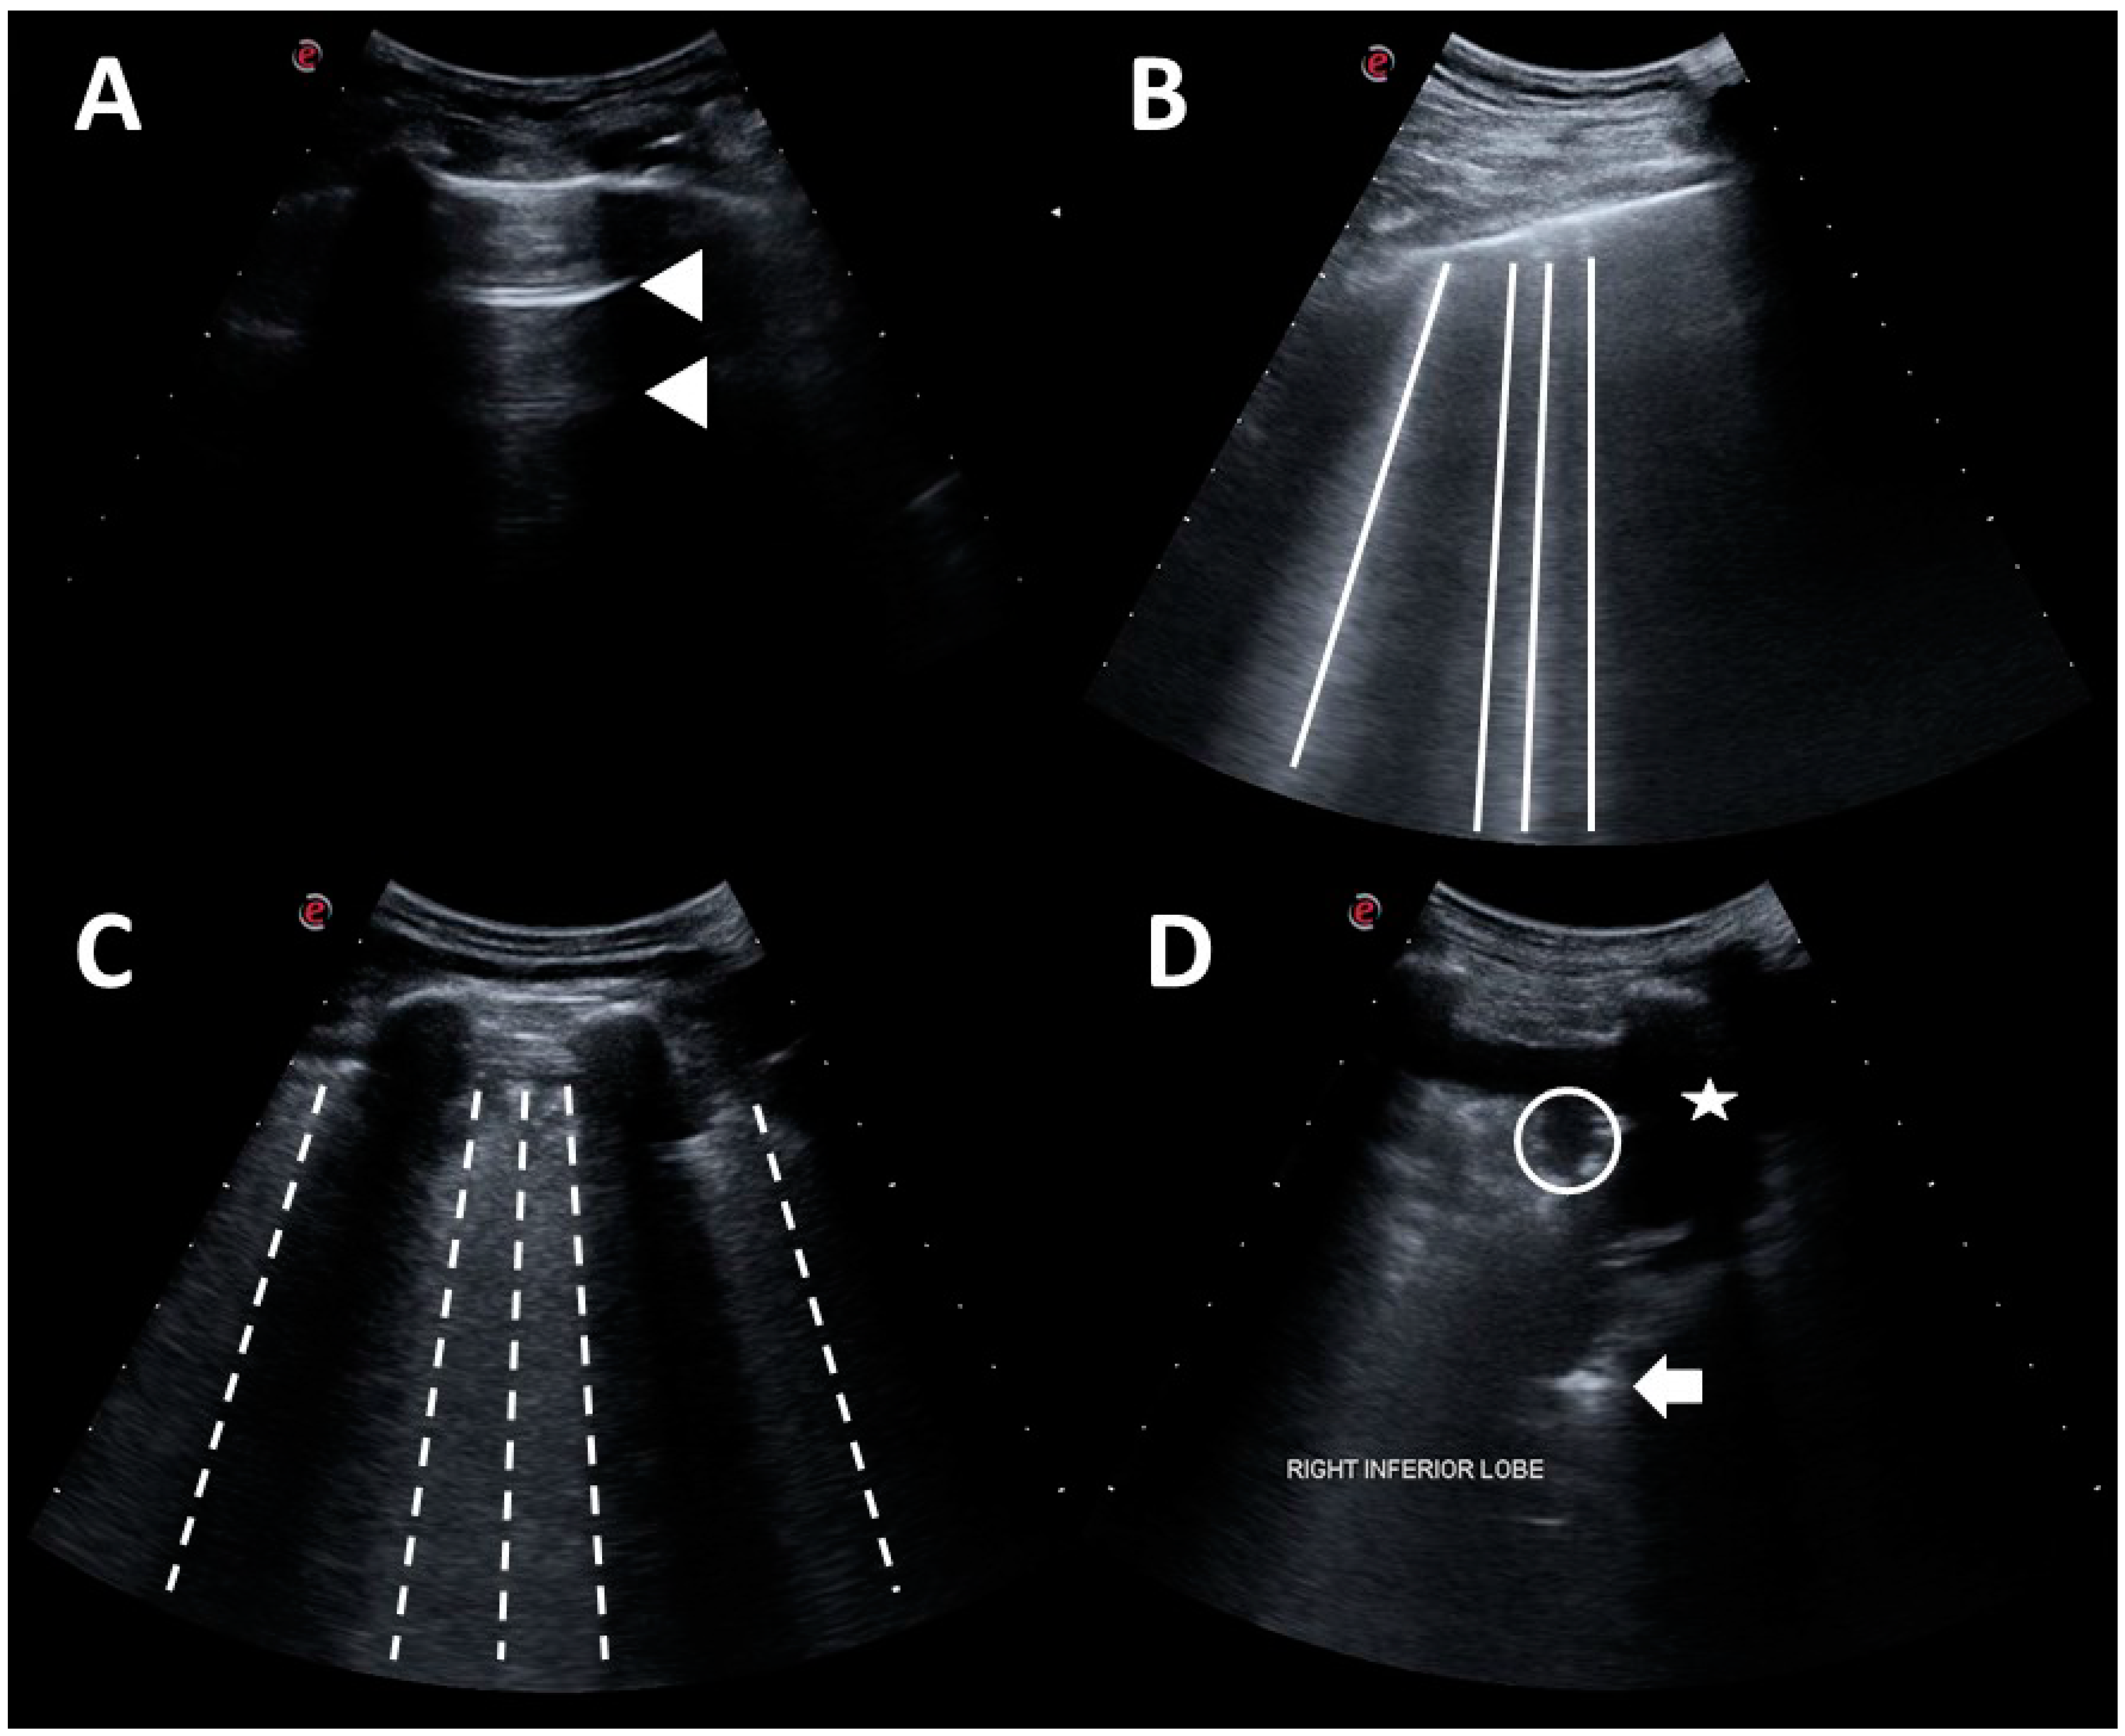

2.3. Lung Ultrasound

2.4. Automated Algorithm